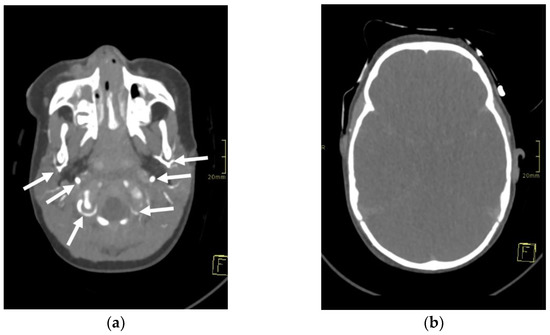

CEUS was performed as an ancillary imaging test for the confirmation of brain death. Before the examination, the details of the examination and the risks for the patient were explained to the child’s guardian. Written informed consent was obtained from the child’s guardian to perform the brain CEUS scan. The examination was performed by a paediatric radiologist with 2 years of subspecialty experience in paediatric brain imaging and 4 years of experience in performing CEUS examinations. For the examination, a Mindray M9 ultrasound scanner with a 1.4–5.1 MHz convex ultrasound transducer was used (Mindray, Shenzhen, China). SonoVue (Bracco, Milan, Italy) was used as the contrast agent. The anterior fontanelle was used as the acoustic window to scan the brain in the coronal and sagittal planes. Firstly, pre-contrast grey-scale imaging was performed to optimise the image. After that, a contrast-specific imaging mode and a low dynamic mechanical index (MI) of 0.06–0.07 was used for the scanning during the CEUS examination. To enable the simultaneous attachment of the US contrast agent and saline to the line, to avoid any delays in flushing the line with a saline flush, a three-way stopcock was connected to the existing peripheral intravenous line. At the start of the examination, 0.3 mL of US contrast agent, followed by a saline flush, was intravenously applied through a peripheral line. Only one bolus of US contrast agent was administered during the examination. For the first 60 s after the contrast administration, a continuous cine clip was obtained in the coronal plane at the level of the third ventricle, including the frontal horns of the lateral ventricles and heads of the caudate nuclei bilaterally. After that, intermittent images were obtained during the next 10 min in order to assess brain perfusion and avoid excessive contrast microbubble destruction from continuous imaging. The CEUS examination showed enhancement of the extracranial vessels and a lack of enhancement of the intracranial vessels (Figure 2). Only a scant amount of contrast microbubbles was observed within the left middle cerebral artery and pericallosal artery during the examination (Figure 3). After 10 min, we observed complete microbubble clearance and finished with the examination. The brain CEUS examination was performed in a paediatric intensive care unit at the bedside, and the whole procedure, including preparation, lasted approximately 15 min. No adverse effects were observed after the intravenous application of US contrast agent.

Figure 2. Midcoronal contrast-enhanced ultrasound images of a 1-year-old infant’s brain obtained (a) 10 s and (b) 69 s after the contrast administration. Both images demonstrate a lack of enhancement of the intracranial vasculature and no brain perfusion. (c) Normal CEUS brain scan in another infant is shown as a comparison.